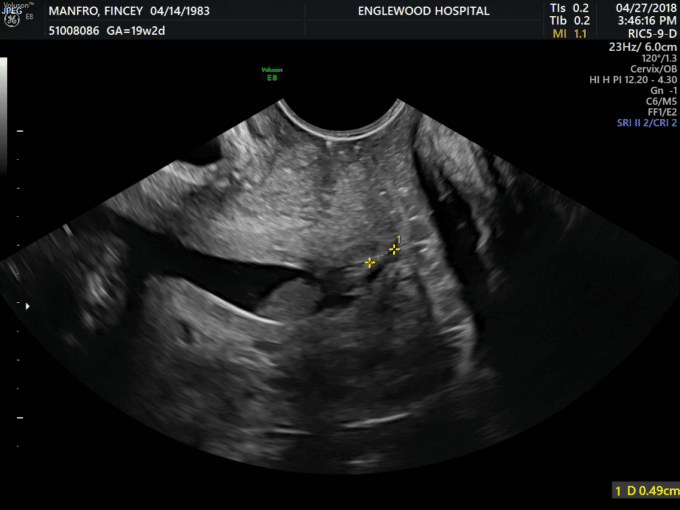

From www.trialexhibitsinc.com

Ultrasound of a Short Cervix TrialQuest Inc. Short Cervix Things To Avoid Lifting heavy objects can strain your pelvic area and put pressure on. Health care providers may recommend a few different methods to help avoid premature birth. Learn what to expect when diagnosed and how you might. Here are some things to avoid if you have a short cervix: But if you have a very short cervix, 20 mm (0.8 in.). Short Cervix Things To Avoid.